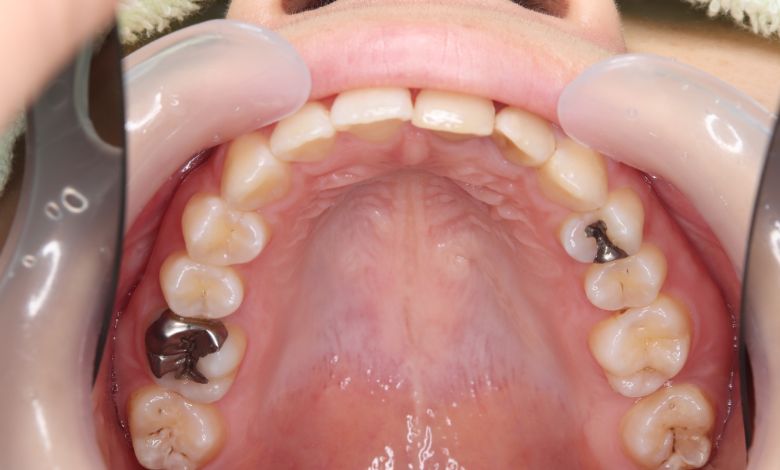

正常な咬合関係が確立され、前歯の自然なアーチと歯軸も整い、歯列全体が滑らかなカーブを描く美しい歯並びに

精密検査の結果、当院では抜歯を行わず、歯列弓の拡大によってスペースを確保し、非抜歯での矯正治療を選択しました。歯列の叢生(ガタガタ)は解消され、機能的かつ審美的に優れた咬合が得られました。

叢生が解消され、歯列全体にわたり滑らかで調和のとれた配列が得られています

歯列弓はV字型から自然でゆったりとしたU字型へと広がり、唇側に転位していた犬歯も正しい歯列内に整列されています。